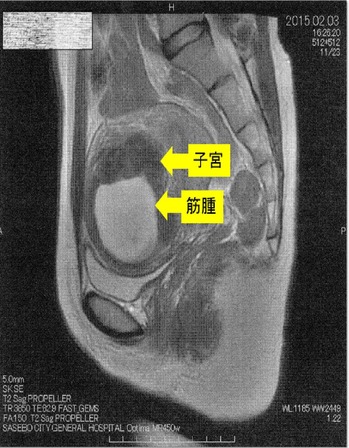

´ÁÊýÌô¤Ç»ÒµÜ¶Ú¼ð9Ѥ¬7ѤËÀ¸ÍýÄˤâ¿Î̽зì¤â²þÁ±¼ê½Ñ²óÈò¤Ç¤¹¡£¶Ú¼ð¤ÎMRI¼Ì¿¿¤Ç¤¹

¡Ú2015ǯ2·î3Æü¡¡£Í£Ò£É¼Ì¿¿¡Û

¢¨Çò¤¤Éôʬ¤¬¶Ú¼ð¡¢¼þ¤ê¤ÎÉôʬ¤¬»ÒµÜ¤Ç¤¹¡£